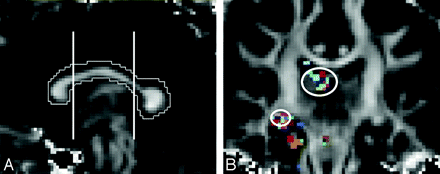

One rater (M.E.A.), who performed tracing of entire fiber tracts, was blinded to all clinical data, including group membership of subjects in control or patient groups and the side of the seizure focus. The following fiber tracts were traced (Fig 1): cingulum fibers within cingulate gyrus (CG), parahippocampal fibers within parahippocampal gyrus (PH), superior longitudinal fasciculus (SLF), inferior longitudinal fasciculus (ILF), UF, FORX, anterior thalamic radiations (ATR), and inferior fronto-occipital fasciculus (IFOF). The algorithms for obtaining most of the fiber tracts are described by Wakana et al.38 This multiple region of interest method uses “OR,” “AND,” and “NOT” operations to show all fiber tracts within a region of interest, find shared tracts within 2 regions of interest, and remove unnecessary fibers, respectively. This method has shown high reproducibility and was used to obtain the CG, PH, SLF, ILF, UF, ATR, and IFOF. However, the SLF and CG were slightly modified as follows: All SLF fiber tracts within the external capsule were removed by multiple “NOT” operations. For CG, “OR” regions of interest were drawn in the coronal plane in the region of CG at the level just posterior to the genu of the corpus callosum (CC) and anterior to the splenium of CC, with “AND” argument placed at the midpoint of CC (Fig 2A).

A, For CG, “OR” regions of interest were drawn in the coronal plane in the region of CG at the level just posterior to the genu of the CC and anterior to the splenium of CC, with “AND” argument placed at the midpoint of CC. B, Order of “OR” region-of-interest selection in a coronal section to obtain right FORX fiber.